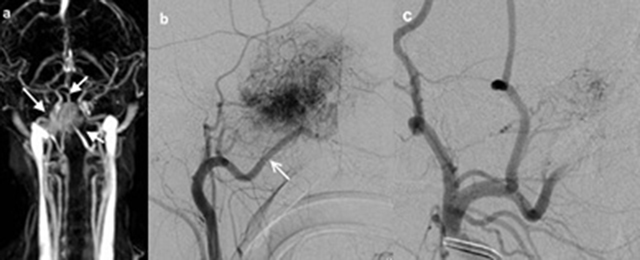

Figure 2

10-year-old male patient (patient 3), (a) TWIST-MR angiography of the patient showed bilobule hypervasculer mass on the right side (white arrows). (b) Selective right carotid artery angiography shows that JNA is supplied with the right internal maxillary artery (white arrow). (c) It is observed that the opacification of JNA mainly dissappeared in the angiography display obtained after the internal maxillary artery was embolized with microcoil.